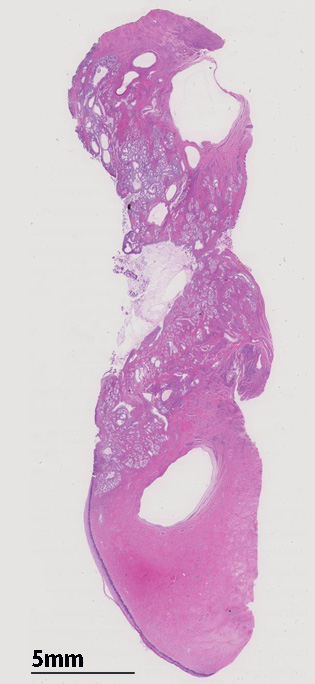

子宮頚管腺に類似した高円柱上皮よりなる腺管の著明な増生を認める。これらは大型で拡張した導管様腺管と,それを囲繞するように配列する分葉状構造をしめす小型腺管からなり, 嚢胞状に拡張した腺管も随所に認められる。最深部にみられる腺上皮は, 嚢胞状に拡張した腺管の一部と考えられる。

増生腺管上皮の細胞質は淡明ないし淡好酸性で, 核は小型で基底側に配列し、明らかな異型や重層化, 核分裂像を認めない。

腺管が破綻し, 間質への粘液逸脱と、それに対する間質反応も認めるが, この部分でも細胞異型は見られない。

間質の一部には炎症細胞浸潤がめだつ。間質浸潤を疑う「折れ釘-->いびつなおれ釘のようなねじれた--」のような不整な形態の腺管は認められない。

LEGHは大型導管に類似した拡張腺管の周囲に中型から小型の腺管が分葉状に増生するのが特徴。小型腺管を構成する高円柱上皮細胞質は正常頸管腺上皮の細胞質が淡明あるいは, やや青白い色調を呈するのに対し淡明ないし淡好酸性となる傾向にある。

loupe像では, 拡張した導管を中心に高円柱上皮からなる腺管が分葉状に配置する所見が認められる。